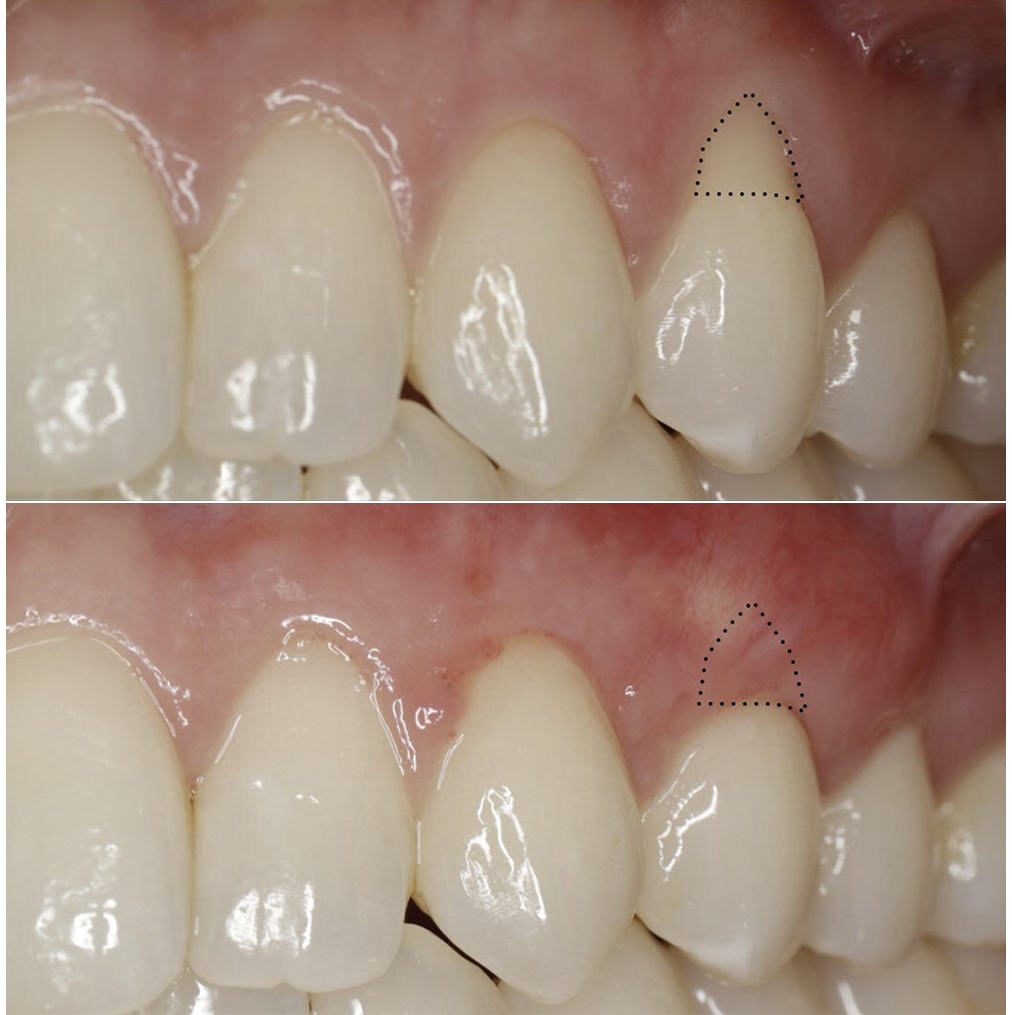

Patient had severe sensitivity on single tooth, patients own tissue was used to cover the sensitive root for a natural healthy & stable coverage

Lower front tooth was sensitive to cold drinks and brushing, patients own tissue was used to cover the sensitive root for a natural healthy & stable coverage

Patient realized her front teeth were loosing gum and every year it was getting worse. patients own tissue was used to cover the sensitive root for a natural healthy & stable coverage

Lower front tooth was sensitive brushing, it happened quickly as a result of plaque buildup on the tooth. Patients own tissue was used to cover the sensitive root for a natural healthy & stable coverage

Upper left canine has recession from muscle pull. Patients own tissue was used to cover the sensitive root for a natural healthy & stable coverage

Patient own tissue used to cover the roots. Using your own tissue provides the best color match along with longest stability

Patient had clefting of the gum tissue from improper flossing technique. Patient own tissue used for root coverage for long lasting stability along with oral hygiene instruction

Lower front teeth had severe recession do to patient bite. Patient own tissue from root of the mouth was used to rebuild the tissue, cover the root and patient was referred to orthodontist for alignment of teeth

Lower teeth started getting recession and patient was super sensitive. CTG was performed to make the gums thicker and provide a stronger barrier against recession

Very thin tissue, roots on the lower teeth super sensitive, Connective tissue graft used to cover the roots and provide a natural look and protection

Very thin tissue, roots on the lower teeth super sensitive, Connective tissue graft used to cover the roots and provide a natural look and protection

Single tooth recession, super sensitive, Connective tissue graft used to cover the roots and provide a natural look and protection